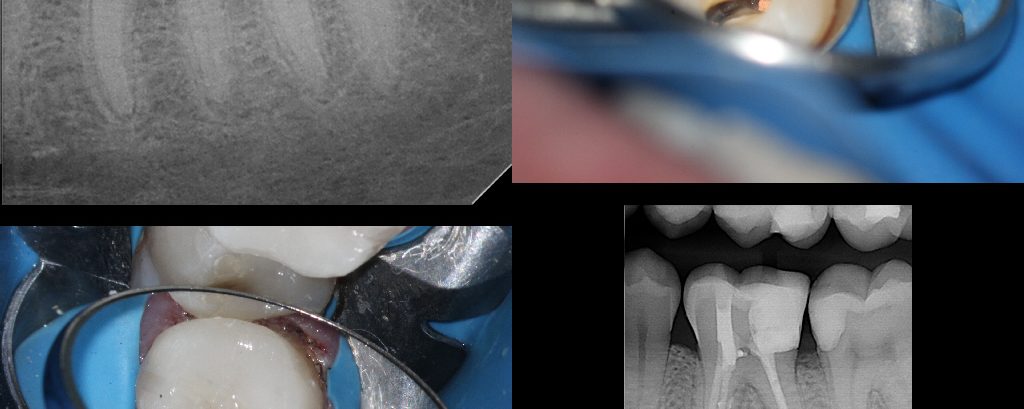

65 year-old female in good health.  Root canal treatment was completed by my predecessor 15 years ago.  She lost the post/crown two weeks ago.  Tooth is asymptomatic.  Referring doc asked if I would “do one of your magic cores so we can hold onto this tooth for a little bit longer.”  No problem.